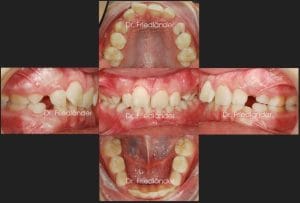

Fotos iniciales de la boca del paciente

Tratamiento con ortodoncia fija y microtornillos (Mordida abierta) – Caso 42. Hoy presento un tratamiento de un paciente con mordida abierta que acude a nuestro centro para una primera visita. El paciente acude para pedir otra opinión tras recibir varios opiniones sobre su tratamiento que no le han convencido (planes de tratamiento como cirugía ortognática o extracciones o simplemente tratamiento con brackets de autoligado tipo Damon); además de la mordida abierta, el paciente presentó dolores de ATM (la articulación de la mandíbula).

Después de estudiar el caso comentamos con el pacientes todas las opciones que tenemos para solucionar su maloclusión. Las opciones de tratamiento con cirugía ortognática o extracciones dentales fueron descartads ya que este caso se puede solucionar correctamente con microtornillos de anclaje. Para intruir los molares superiores y distalar ligeramente la arcada inferior, para mejorar el engranaje de la boca, se utilizan 4 microtornillos colcoados detras de cada muela (2 arriba y 2 abajo). Este tipo de tratamientos de ortodoncia pertence a un grupo de tratamientos que utilizan el anclaje distal con microtornillos para mover los dientes hacia donde nos convenga más. En este caso de clase II usamos anclaje distal para mover hacia atrás los molares superiores y en este caso de clase II con mordida abierta tratado con ortodoncia lingual usamos el anclaje distal con microtornillos para mover los molares superiores hacia arriba y hacia atrás lo que ayudo a cerrar la mordida abierta.